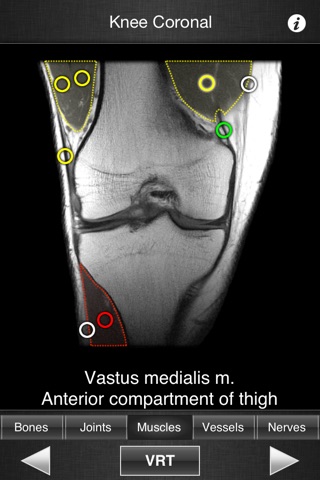

This application is designed for healthcare professionals (Radiologists, General Practitioners, Orthopedists, Surgeons, Physiotherapists among others) as well for students, as a reference and learning tool. It contains 82 contiguous knee MR slices (4-5 mm thickness) in the three anatomical planes.

- The five different display modes available (bones, joints, muscles, blood vessels and nerves) facilitates label visualization.